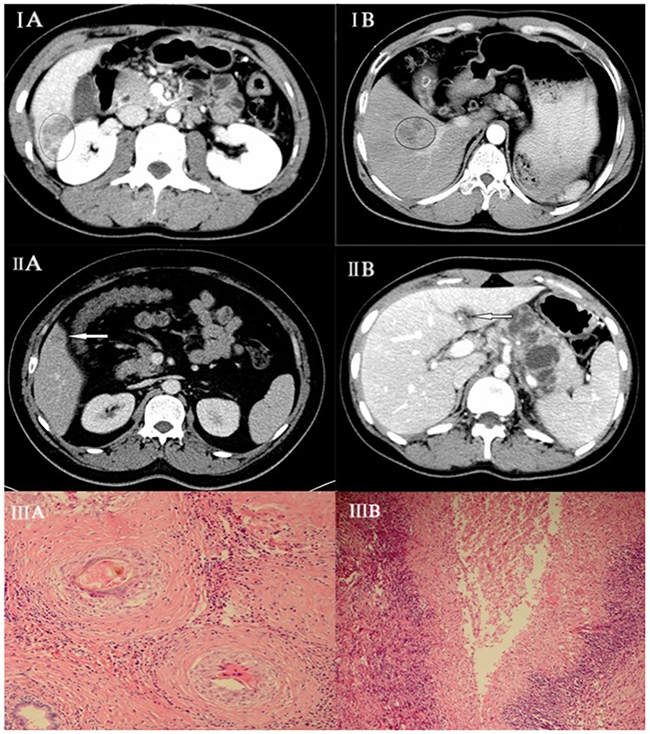

In the paragonimiasis group, 75% (21/28) of the lesions detected on MDCT were subcapsular. The lesions were distributed among segments VIII (28.6%; 8/28), VII (21.4%; 6/28), VI (17.9%; 5/28) and V (14.3%; 4/28), respectively. 57.1% (16/28) of the lesions were tubular or tunnel shaped (Figure IIA, IIB). All the lesions were hypoechoic. 71.4% (20/28) of the lesions showed rim enhancement with irregular tract-like non-enhanced internal areas and formed characteristic target loop whereas 17.9% (5/28) lesions were homogenously enhanced and 11% (3/28) lesions were non-enhanced.

Figure 1: (IA) Hepatic paragonimiasis in a 50-year-old male patient. Enhanced MDCT scan at portal venous phase shows heterogeneous enhancement. (IB) Hepatocellular carcinoma in a 45-year-old female. Enhanced MDCT scan at portal venous phase shows homogeneous enhancement. (IIA) Hepatic paragonimiasis in a young male. Enhanced MDCT scan at portal venous phase shows solid, ring-enhancing with forming target loop as indicated by the arrow. (IIB) Image shows tubular formation in early phase of paragonimiasis as indicated by the arrow. (IIIA) Pathological finding showing an egg being engulfed by a macrophage with coagulative necrosis within the lesion surrounded by (IIIB) infiltration of a large number of barrier-like arrayed epithelioid cells.

In the HCC group, 37 lesions were detected on MDCT. 59% (22/37) of HCC lesions were located in segments III, IV or VII and only 10.8% (4/37) lesions were subcapsular. All the lesions were solid and regular shaped. In the CT scan, all the lesions were hypoechoic with 94.6% (35/37) showing homogenous enhancement in arterial and venous phase (Figure IB).

The diagnosis for paragonimiasis in the liver is based on the pathological analysis of the biopsy that considers (1) coagulative or liquefactive necrosis within the lesion; (2) infiltration of a large number of eosinophils forming chronic eosinophilic abscesses and sporadic distribution of Charcot-Leyden crystals; and (3) hyperplasia of granulomatous and fibrous tissue around the lesion (Figure IIIA, IIIB).